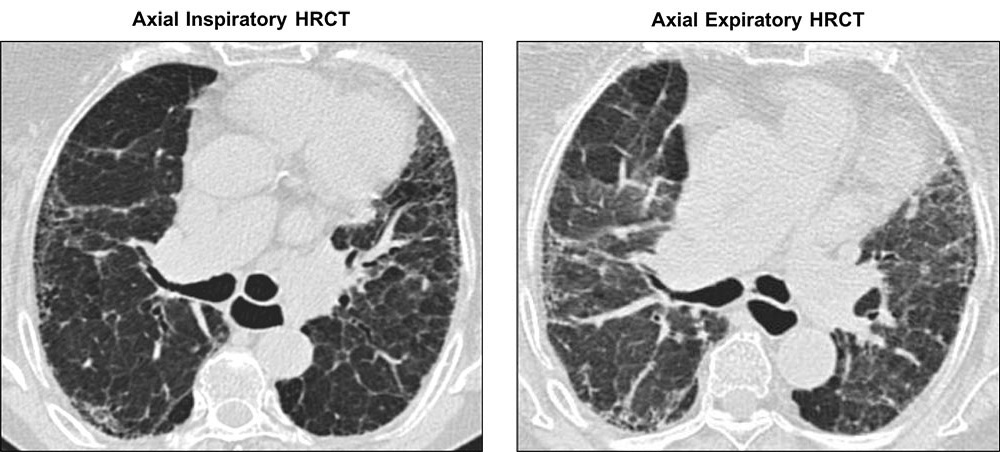

Axial inspiratory and expiratory HRCT images showing air trapping in a patient with chronic hypersensitivity pneumonitis. In the inspiratory image to the left, the lung parenchyma is abnormal with apparent architectural distortion and reticulation in a subpleural distribution. Also present is mild traction bronchiectasis and areas of obvious opacity, reticulation, and volume loss, suggestive of fibrosis. In the expiratory image, there are areas of increased blackness which have failed to empty their air on expiration, indicating air trapping. The finding of air trapping is suggestive of a pattern other than usual interstitial pneumonia (UIP).

Images courtesy of and used with permission from Jonathan Goldin, MD, PhD.